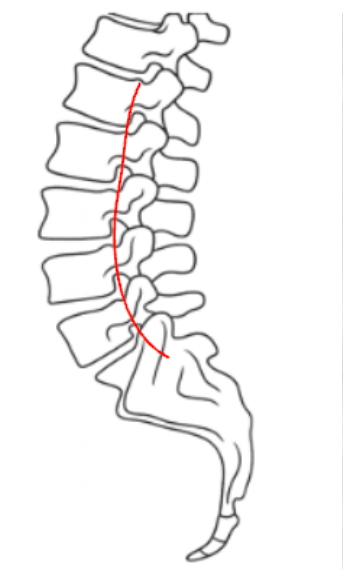

George’s Line—also known as the Posterior Vertebral Body Line—is a sagittal alignment assessment used to evaluate vertebral body translation and spinal stability.

It is drawn along the posterior margins of each lumbar vertebral body on a lateral X-ray and should form a continuous, smooth curve from L1 through the sacrum.

Any disruption or step-off between adjacent vertebrae suggests anterior or posterior displacement—commonly associated with spondylolisthesis, fracture, or ligamentous injury.

• A smooth curve indicates normal alignment.

• A step-off or break indicates vertebral translation.

George’s Line is part of the three-line lumbar assessment, alongside the anterior vertebral line and spinolaminar line, providing a quick screen for sagittal integrity.

Step-offs correspond to vertebral translation seen in degenerative spondylolisthesis, traumatic subluxation, or pars defects.